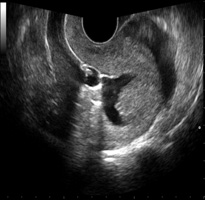

OFollicular Monitoring (फॉलिक्युलार मॉनिटरिंग) सोनोग्राफीच्या मदतीने अंडाशयाची होणारी वाढ बघणे

S.S.G(सोनोसालफिंगोग्राफी) गर्भाशयात विशिष्ट प्रकारचे औषध सोडून सोनोग्राफीच्या साहाय्याने गर्भाशय व नळयाची तपासणी